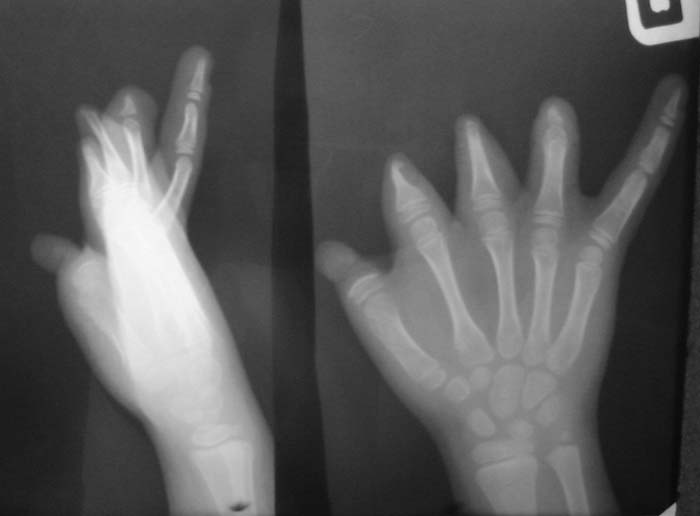

Уважаемые коллеги!Девочка, 6 лет. Врожденная аномалия развития кистей и стоп.Вопрос: лечение?В приложении - рентгенограммы и клинические фотографииЗаранее благодарен!С уважением,А.В.Владзимирский

Без рентгенограмм костей левой стопы, голени и голеностопного сустава определение тактики лечения левой нижней конечности невозможно. А с кистями рекомендую направить в специализированное отделение института им.Турнера (для удлинения фаланг пальцев с использованием микрохирургической техники)e-mail института им.Турнера: turner@admiral.ru

Безусловно девочке необходимо создать 1-й палец правой кисти - создать противопоставление остальным пальцем и таким образом получить функцию захвата. Варианты операций:

1. Пересадка 2-го пальца стопы (предварительно сделав доплерографию стопы и кисти)

2. Транспозиция культи 3 или 4-го пальца в положение 1-го.

3. Несвободная пересадка комплекса тканей на a. radialis в который входит участок лучевой кости (реверсионный лучевой лоскут с костным фрагментом для восстановления 1-го пальца.

4. Возможна свободная костная пластика (например, фрагмент в/3 большеберцовой кости кости с одновременной кожной пластикой по Блохину-Конверсу.